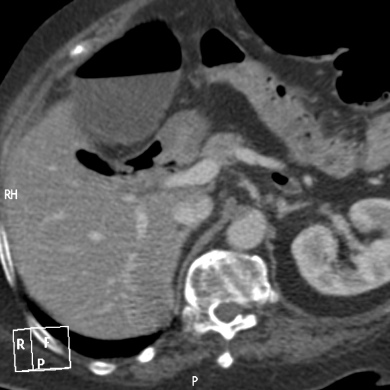

Lipoma intestinal: frecuente como punto guía o cabeza de invaginación en el instestino delgado. Aquí presentamos un caso de lipoma intraluminal en el colon, que producia obstrucción y cambios inflamatorios en el colon ascendente.